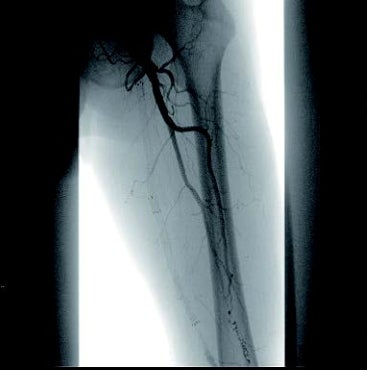

[治療] 右総大腿動脈(common femoral artery:CFA)を逆行性にエコーガイド下に穿刺。山越えで左 CFAまで6 Frガイディングシースを進めた。造影で左SFA起始部付近からベアステント遠位端のやや中枢側まで、TOSAKA分類3のISO病変があることを確認した。ところどころ病変が硬く、0.014 inchガイドワイヤーの先端2.8 gと先端12 gを順次使用して閉塞部位を突破した。PTAバルーン4 mm × 250 mmで前拡張したのち、病変部をカバーするように左SFA末梢側から左SFA起始部にかけてバイアバーン® ステントグラフト6 mm × 250 mmと6 mm × 100 mmを留置し、閉塞したベアステントをフルカバーした。バルーン5 mm × 220 mmで後拡張を実施、血管内超音波(IVUS)と造影で病変部の良好な拡張、血流を確認し手技を終了した(図3)。足関節上腕血圧比(ABI)は0.68から0.92に改善した。さらに6年が経過し、間欠性跛行の再燃があり、ステントグラフトは開存していたが(図4-1)、さらに末梢の膝窩動脈での石灰化プラークによる閉塞病変(図4-2)が原因と考えられた。アテレクトミーデバイスとDCBで膝窩動脈病変を治療して症状は消失した。run offが不良であったにもかかわらず、中枢側のステントグラフトが6年間開存していたことは特筆すべきことである。同患者については現在まで15年にわたり経過をみているが、経年的に動脈硬化が進んでおり、通常のステントやバルーンでの治療部は再治療を繰り返している。その中でステントグラフトを留置した長区間ISO病変は6年間開存を保っていたというのは、物理的に内膜過形成をシャットアウトするステントグラフトでしかみられない現象であると思われる。ISO病変に対するバイアバーン® ステントグラフトの使用が保険適用されるようになったことは、血管内治療医や患者に福音をもたらしたのではないだろうか。